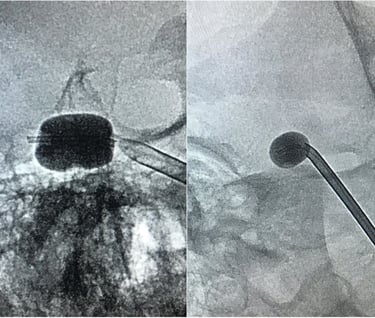

Gehirnaneurysma (Clip, Coil, Flow Diverter)

Trigeminusneuralgie (Mikrovaskuläre Dekompression und Ballon-Rhizotomie)

Vaskuläres und Endovaskuläres Fellowship: Beth Israel Deaconess Medical Center, Harvard University, Boston, Massachusetts, USA

Als klinisch-wissenschaftlicher Neurochirurg habe ich großes Interesse daran, meine klinischen Aufgaben durch Wissenschaft und Forschung in den von uns behandelten neurochirurgischen Erkrankungen zu ergänzen. Seit meinem Studium und postgraduellen Ausbildung war ich an Grundlagenforschung, klinischer und translationaler Forschung beteiligt und habe bisher mehr als 450 wissenschaftliche Veröffentlichungen zur medizinischen Fachliteratur beigetragen sowie erfolgreich kompetitive Drittmittel eingeworben. Wir haben die Behandlung traumatischer zerebrovaskulärer Erkrankungen, genetische Polymorphismen im Zusammenhang mit zerebralen Aneurysmen und aneurysmatischen Subarachnoidalblutungen sowie die Behandlung von Thrombozytenaggregationshemmern im Zusammenhang mit der Flow-Diverter-Behandlung von zerebralen Aneurysmen untersucht, um nur einige Projekte zu nennen.